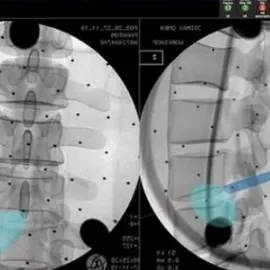

For many years, microscopic discectomy, spinal fusion, and recently total disc replacement have been the surgical approaches utilized for addressing disc herniations or recurrent herniations...